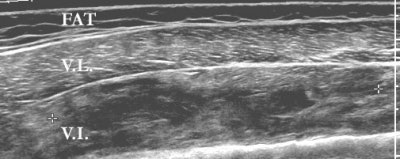

Sonography was performed with the clinic’s HDI 5000 SonoCT scanner (Philips Medical Systems, Bothell, WA) using a panoramic field of view. The vastus lateralis showed normal echogenicity throughout. The muscle under it, the vastus intermedius, was heterogeneous in echogenicity and was consistent with edema.

"So you have a beautiful, perfectly normal vastus lateralus, and then deep to it, we have a diffusely abnormal vastus intermedius. It’s got a lot of abnormal signal within it, but it’s not completely torn. You can say it’s all extensive interstitial tearing," Crim said.

| Coronal ultrasound image of the lateral thigh. Image was obtained using a panoramic field of view. The superficial muscle, the vastus lateralis (VL), shows normal echogenicity throughout. The muscle deep to it, the vastus intermedius (VI), is heterogeneous in echogenicity, consistent with edema. Markers delimit a 16-cm-long region with multiple fluid collections which represents more focal hematoma. |